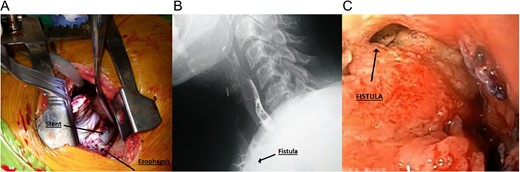

(A) Metal stent seen during thoracotomy. (B) Cervical fistula seen during esophagogram. (C) Cervical fistula seen during upper endoscopy.

Patient is a 51-year-old woman with past medical history of hypothyroidism. She was complaining of dyspepsia so an upper endoscopy was done, revealing a mass in the greater curvature of the stomach, and a biopsy was taken. Pathology showed a poorly differentiated infiltrating adenocarcinoma with signet ring cells. A total radical gastrectomy reconstructed with esophagojejunal Roux-en-Y anastomosis was done. On the sixth postoperative day, purulent drainage was seen on the abdominal drain. And, an abscess was discovered at the level of the esophagojejunal anastomosis, surgery was required, the abscess was drained and a new esophagojejunal anastomosis was done high in the chest with autosutures. The patient persisted with poor medical condition; so an esophagogram identified a leak at the level of esophageal anastomosis, and after failed endoscopic placement of two metal stents to solve the leak, patient persisted with sepsis. Redo operation was performed and at thoracotomy an anastomotic leak, with free purulent fluid in the pleural cavity was found (Fig. 1A). An exhaustive washing of the pleural cavity was performed, stents were removed, thoracic esophagectomy was done, a feeding jejunostomy was made and a cervical esophagostomy was performed. Patient improved considerably after this, with adequate nutritional management through jejunostomy. She was discharged, and 6 months later she was hospitalized again for intestinal transit restitution with an esophagocoloplasty with interposition of the right colon via substernal route.

On the 13th postoperative day, serous fluid drained through the neck and became purulent a day after. A new esophagogram was done and an esophago-colonic anastomosis leak was discovered (Fig. 1B). An upper endoscopy was performed, localizing the fistula of 12 × 6 mm (Supplementary Video & Fig. 1C).